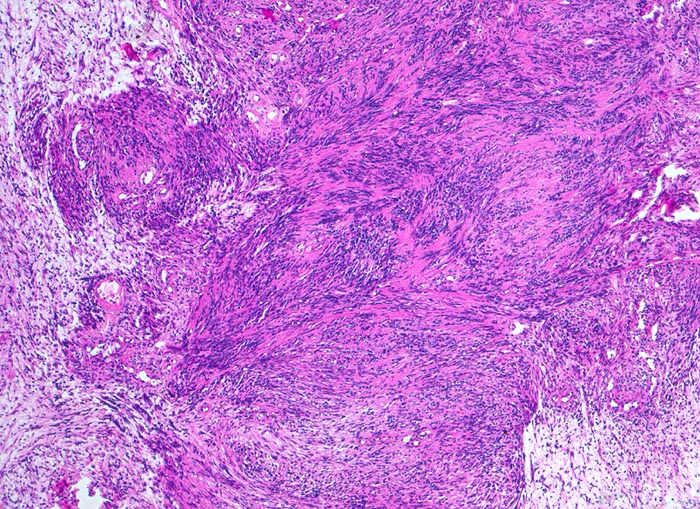

Die histomorphologischen Befunde sind sehr variabel. Am häufigsten bestehen die Tumoren aus Zellzügen mit bipolar orientierten länglichen oder gewellten Kernen und langen Zellfortsätzen. In den sogenannten Antoni A Arealen (> 4295) sind die Zellen in kompakten Bündeln angeordnet, teilweise in Form von Verocay bodies (> 493) (alternierende Anordnung von Kernreihen und Zellfortsätzen). In den Antoni B (> 4296) Arealen bilden die Fortsätze der eher sternförmigen Tumorzellen ein lockeres Geflecht. Einzelne grosse, unregelmässig geformte und hyperchromatische Kerne und flächenhafte Nekrosen, Hyalinisierung oder fokale Verkalkungen sind Ausdruck degenerativer Veränderungen (sogenanntes ancient schwannoma (> 4299)) und dürfen nicht als Zeichen der Malignität fehlinterpretiert werden.

• Biphasischer Tumor mit überwiegend kompakten (Antoni A Muster) und kleinen lockeren, hellen Arealen (Antoni B Muster).

• Antoni A Muster: Parallele Anordnung der Zellkerne und Zellfortsätze (Verocay bodies).

• Antoni B Muster: Lockerer Tumorzellverband mit runden Kernen und spinnwebenartigen Zellfortsätzen.